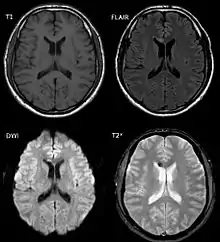

DAI is difficult to detect since it does not show up well on CT scans or with other macroscopic imaging techniques, though it shows up microscopically.[9] However, there are characteristics typical of DAI that may or may not show up on a CT scan. Diffuse injury has more microscopic injury than macroscopic injury and is difficult to detect with CT and MRI, but its presence can be inferred when small bleeds are visible in the corpus callosum or the cerebral cortex.[34] MRI is more useful than CT for detecting characteristics of diffuse axonal injury in the subacute and chronic time frames.[35] Newer studies such as Diffusion Tensor Imaging are able to demonstrate the degree of white matter fiber tract injury even when the standard MRI is negative. Since axonal damage in DAI is largely a result of secondary biochemical cascades, it has a delayed onset, so a person with DAI who initially appears well may deteriorate later. Thus injury is frequently more severe than is realized, and medical professionals should suspect DAI in any patients whose CT scans appear normal but who have symptoms like unconsciousness.[9]

MRI is more sensitive than CT scans, but is still liable to false negatives because DAI is identified by looking for signs of edema, which may not always be present.[33]